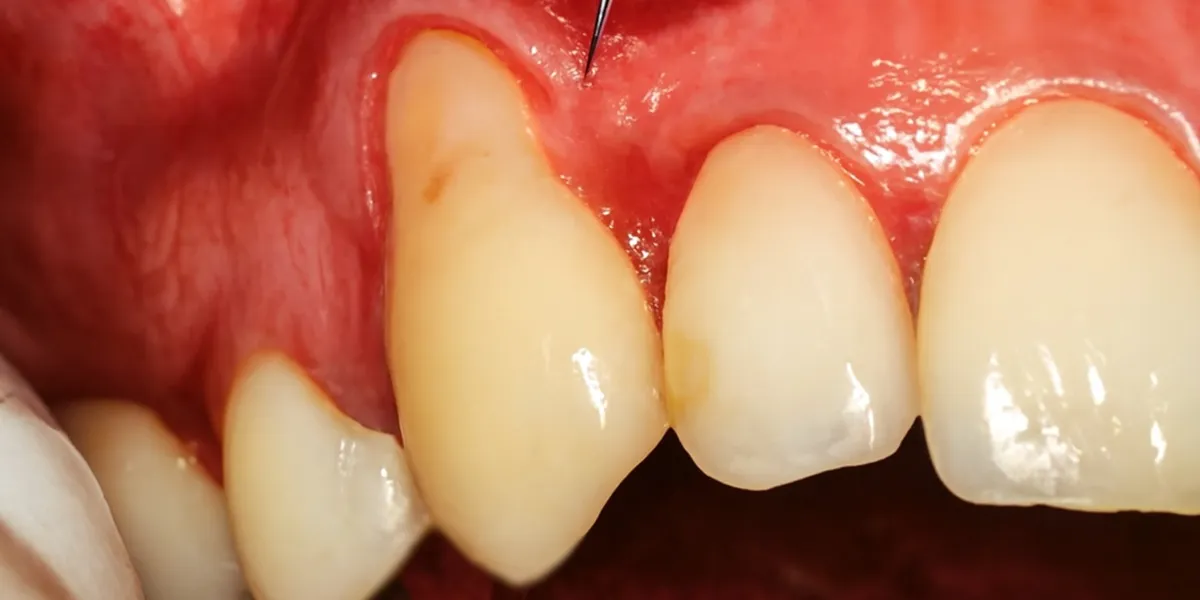

علائم طبیعی بدن در دوران نقاهت جراحیلثه و نحوه برخورد با آنها

در طول دوران نقاهت جراحیلثه، بدن علائمی از خود نشان میدهد که اغلب طبیعی هستند و جای نگرانی ندارند. این علائم نشاندهنده فعال بودن فرآیند ترمیم و پاسخ طبیعی بدن به درمان میباشند. آشنایی با آنها باعث میشود بیمار واکنشهای طبیعی را بهدرستی تفسیر کند.

- تورم خفیف تا متوسط در ناحیه جراحی

- حساسیت به لمس یا تغییرات دما

- تغییر رنگ جزئی لثه در روزهای ابتدایی

- احساس کشیدگی یا فشار ملایم

در صورتی که این علائم بهمرور کاهش پیدا کنند و شدت آنها کمتر شود، نشانه بهبود مناسب و صحیح لثهها خواهد بود.